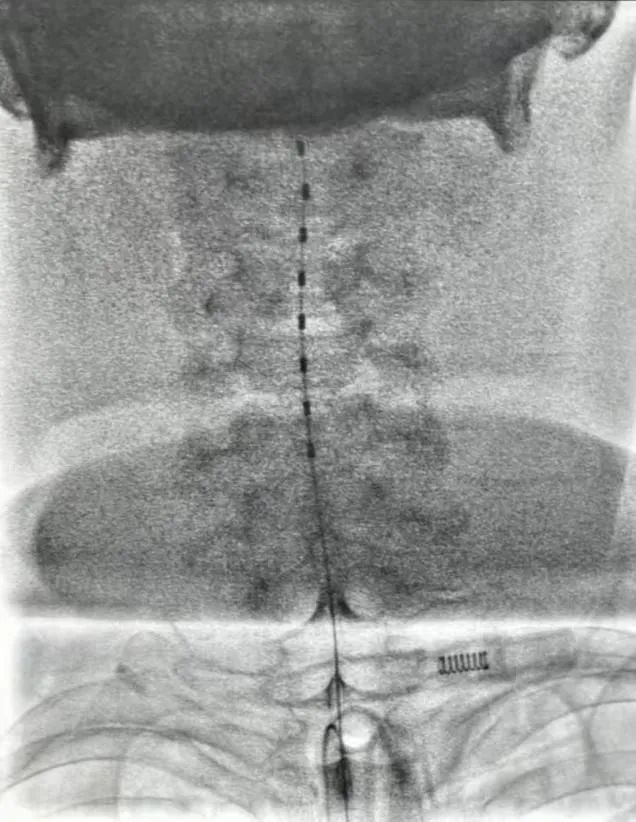

脊髓电刺激(Spinal Cord Stimulation, SCS)是一种将电极植入患者颈部脊髓硬脊膜外,以一定的脉冲电流对脊髓神经进行持续电刺激的新技术。研究证实颈段脊髓电刺激能明显增加脑血流量,减轻脑水肿,增加糖代谢并显著阻止脑萎缩的进程,同时提高脑脊液中多巴胺、去甲肾上腺素水平,减少氧化应激,另外高颈段脊髓电刺激还能激活胆碱能上行网状系统,从而起到促醒的作用。